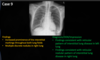

Identify the structures shown here

1 - Aortic Arch (should be ~4 cm)

2 - Pulmonary Trunk

3 - Left ventricle

What is demonstrated by the yellow lines?

What structures are represented by the blue & purple markings?

What condition is likely the cause of these findings?

Pneumonia/Tuberculosis

Identify the structure shown here

Horizontal fissure

What pattern of pneumonia is shown here?

- Bilateral, perihilar area, Irregular

- Bronchopneumonia

- Pink circle = cavitation •associated w/ Infection ie. TB & Tumor)